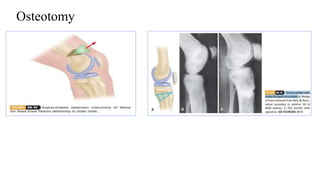

Osteotomy

Lloyd roberts technique of IT

oblique osteotomy

Osteotomy Lloyd roberts techniqueof IT oblique osteotomy